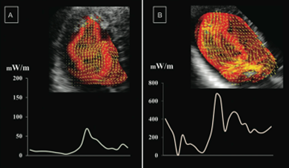

3. 心エコーによるVFM( Vector Flow Mapping)による心臓血管外科手術前後の心腔内血流とenergy loss(エネルギー損失)の評価

VFM( Vector Flow Mapping) は新しいmodality(画像診断技術)で、通常行われる経食道心エコーや経胸壁心エコーで施行可能であり、未だ解明されていない心腔内血流や渦流やenergy loss(エネルギー損失)を評価する事が出来る。これらの評価により、心臓血管外科手術の適応や手術手技の適否の概念を変えることができる研究テーマを推進しています。